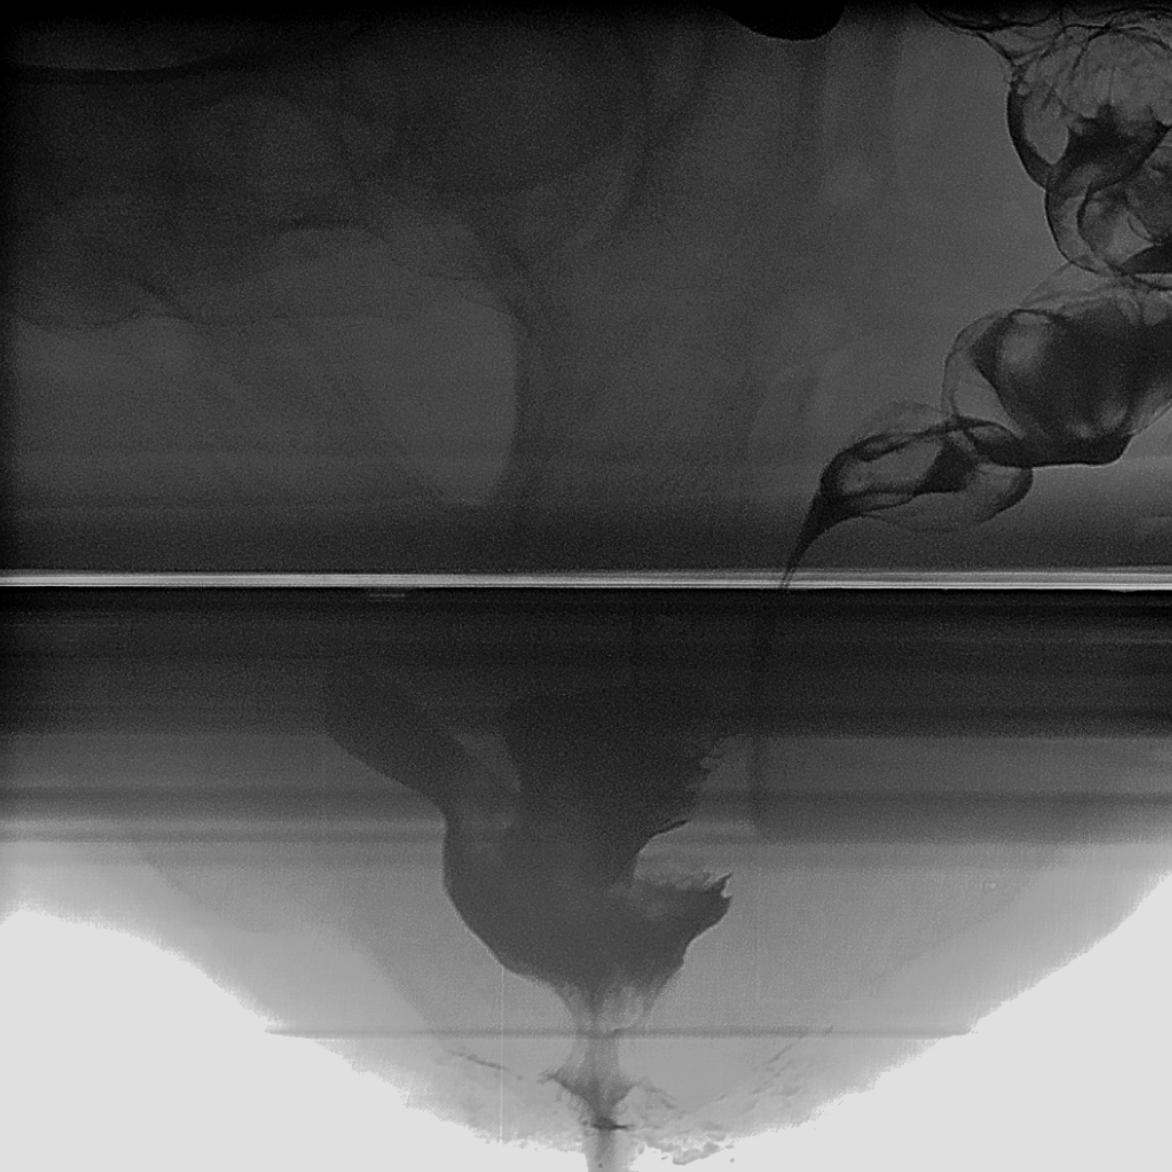

Fluoroscopic Defecography

Use this physiological technique to better correlate symptoms to imaging.